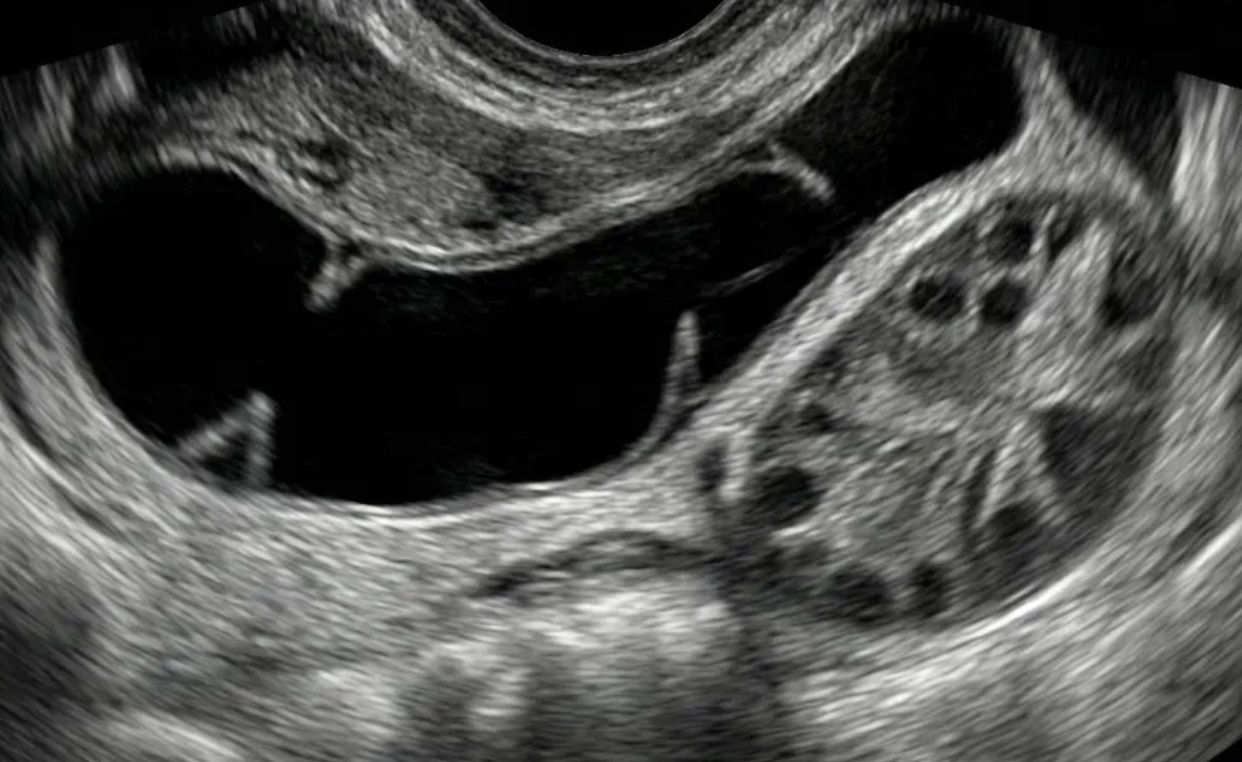

O-RADS US 4 — Risco Intermediário

Risco: 10-<50%Cisto multilocular sem componente sólido ≥ 10 cm ou com IC = 4, cisto unilocular/multilocular com componente sólido, lesão sólida com superfície lisa e IC = 2–3.

Cisto unilocular com componente sólido